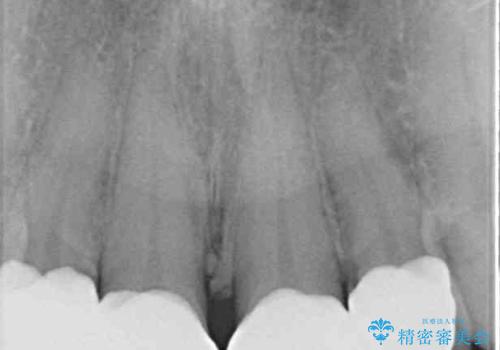

- 自宅近くの歯科医院にて前歯の詰め物が外れたことを機会に、オールセラミッククラウンへの変更を決断して4歯を仮歯に替えたものの、あまりに汚くて恥ずかしいとのことで来院された患者様です。

歯の形成量は不十分で形態は不自然、境目は不適で歯肉が腫れていたため、新しい仮歯に替えた後に歯肉の腫れが引くのを待ち、オールセラミッククラウンにて補綴することとしました。